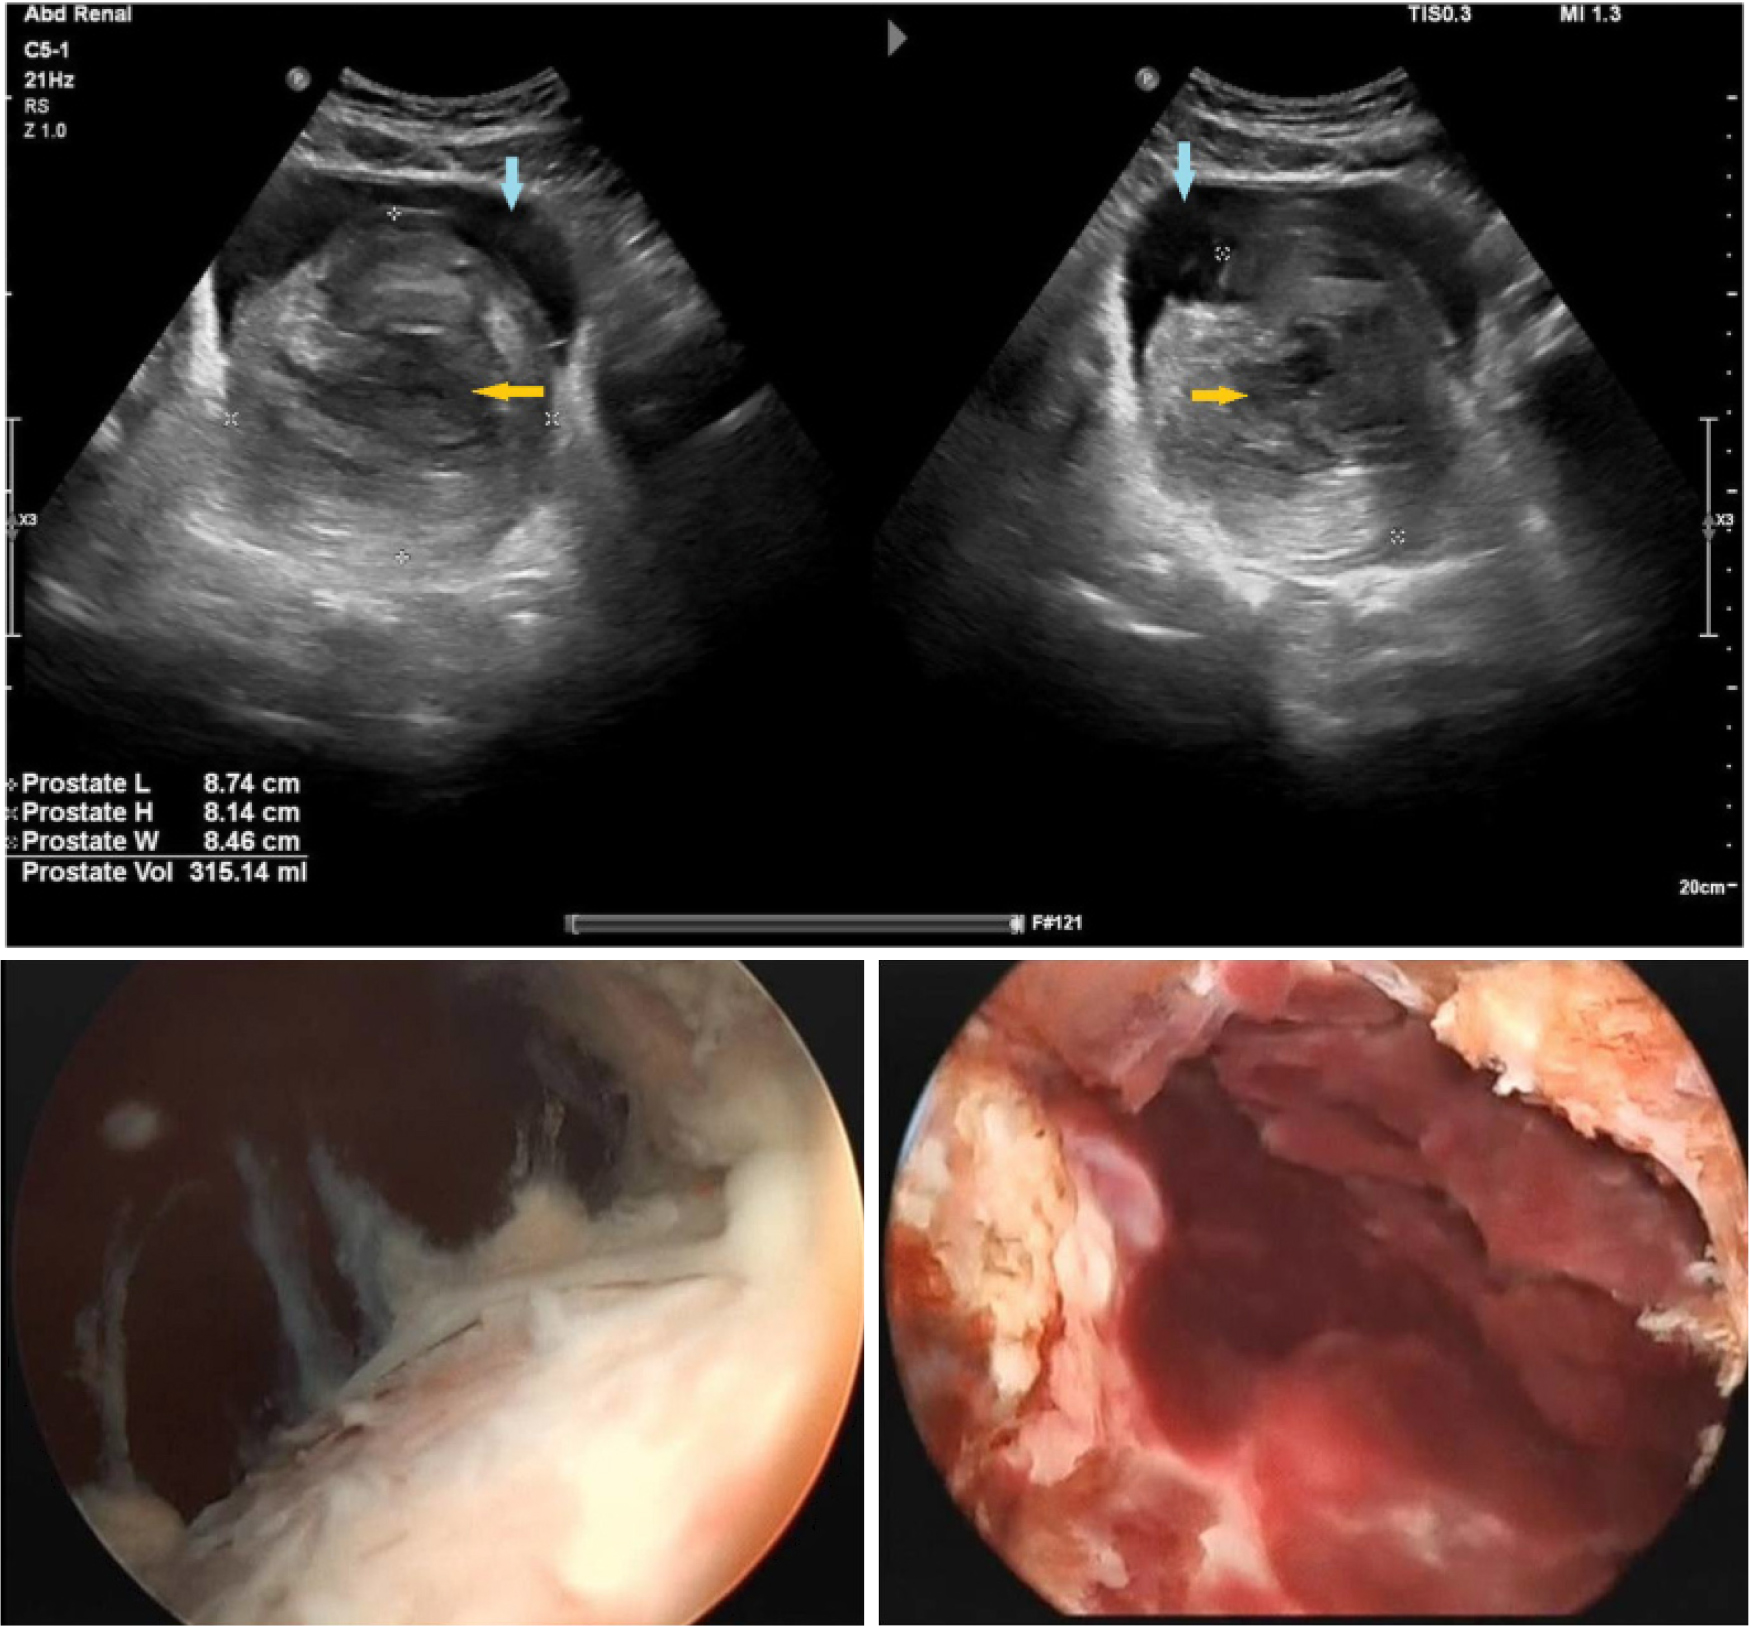

그림 1.

50세 남성에서 Rezum 이후 2주만에 심한 dysuria와 weak stream으로 내원하여 발견된 prostatic urethra의 Sloughed tissue. 이후 TUR로 제거하였다(Alothman A, et al. Cureus. 2020 Nov 27;12(11)에서 인용) [1]